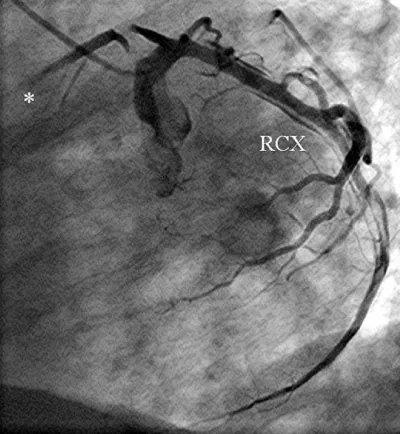

Figure 3: The left coronary artery is shown (right anterior oblique projection) with a long dissection of a large ramus circumflexus (RCX).

Download Image

Figure 4: The left coronary artery shows an occlusion of the left anterior descending coronary artery (*) (left anterior oblique projection, RCX: ramus circumflexus).

A 56-year-old obese man with a history of hypertension was admitted at night to the department of cardiology of our hospital because he had developed sudden onset right-sided thoracic pain with radiation into the right shoulder and right arm. He was sweating profusely and had massive nausea. The initially performed 12-lead ECG showed marked inferior ST segment elevations (Figure 1). Beside analgetics and oxygen, he was treated with aspirin, clopidogrel, heparin and the fibrin-specific thrombolytic tenecteplase. His symptoms resolved after 30 minutes. However, half an hour later, he developed left-sided thoracic pain, tachycardia, low blood pressure and the ECG signs of anterior ST-segment elevation myocardial infarction. The performed coronary angiography revealed a normal right coronary artery (Figure 2). The left coronary artery showed a long dissection of a large ramus circumflexus (RCX) (Figures 3,4). Additionally, the left anterior descending coronary artery (LAD) was occluded at about the mid-level (Figure 4, asterisk). Afterwards the left ventriculography revealed a reduced function and a Stanford type A aortic dissection with the intimal flap (Figure 5, arrows). Immediate patient transfer for emergency surgical intervention was arranged. During transport, ventricular fibrillation occurred, and he required endotracheal intubation as well as prolonged cardiopulmonary resuscitation. Unfortunately, he died due to a refractory cardiogenic shock during further transport.